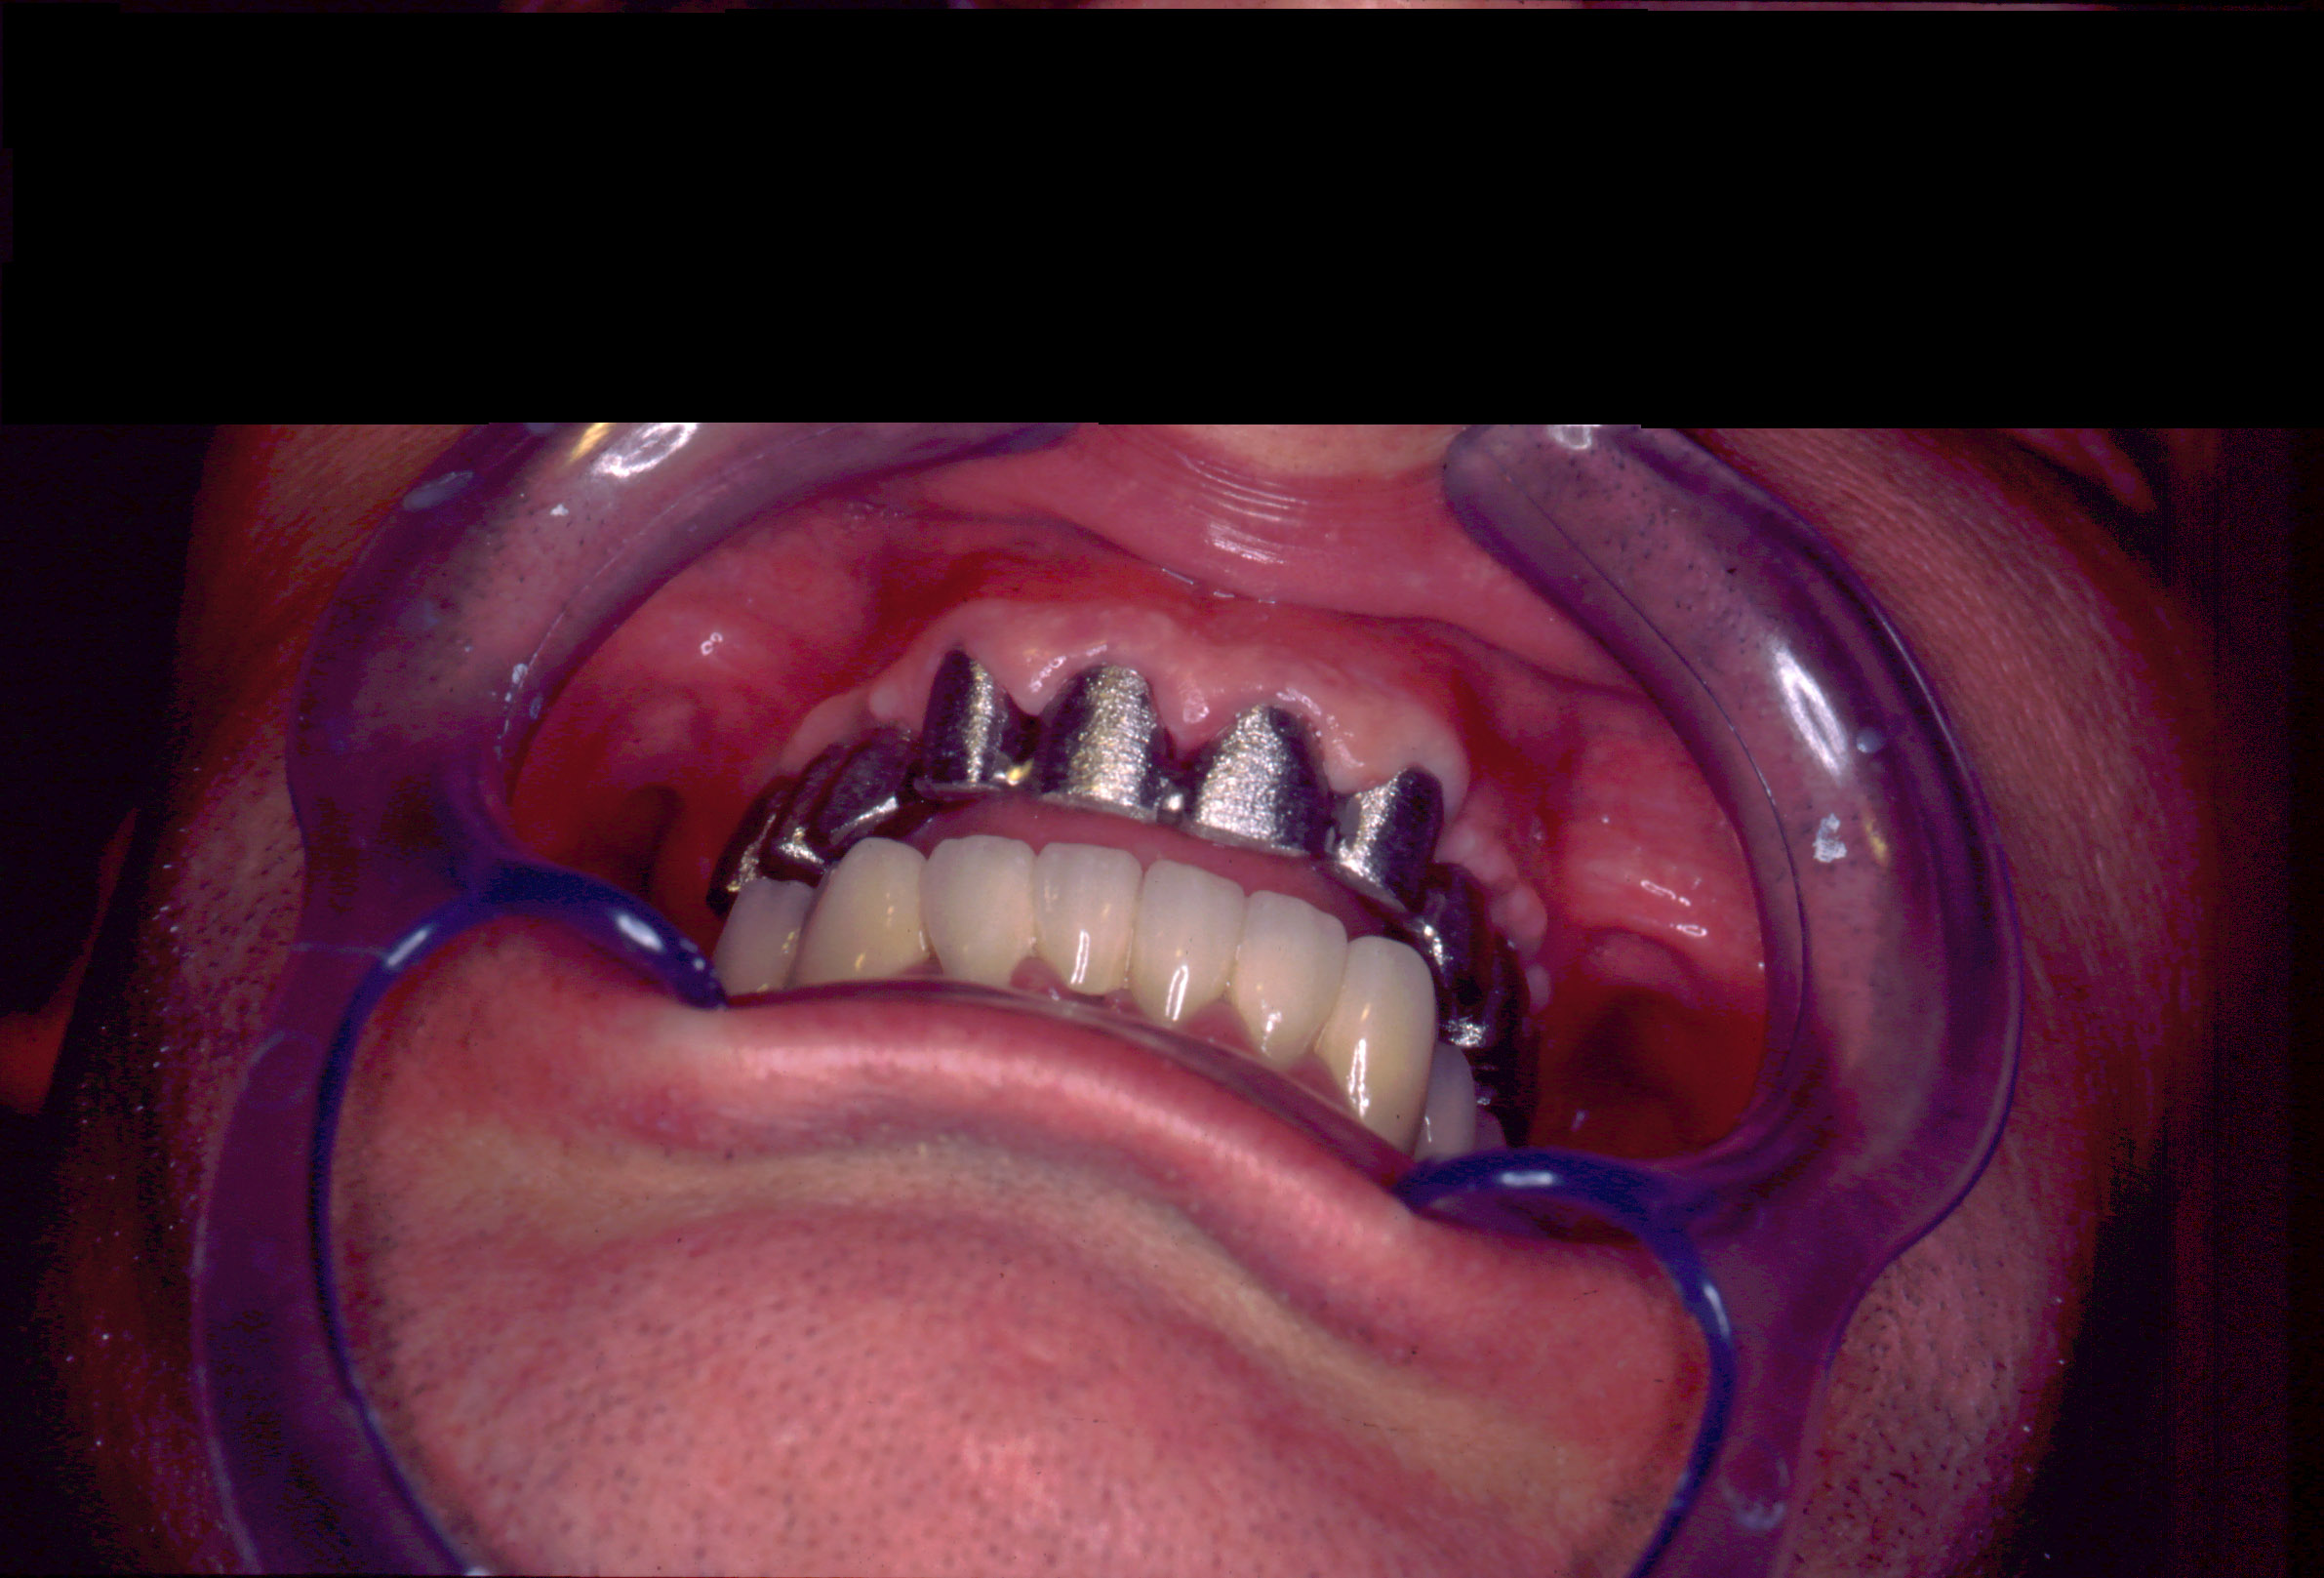

El paciente fue tratado en el año 1994 con una rehabilitación oral. Se instalaron 10 implantes métrica de rosca de conexión 2,3mm : 6 en maxilar superior y 4 en maxilar inferior. En maxilar superior se instalan 3 en segmento distal derecho y 3 en segmento distal izquierdo y permanecen 4 dientes incisivos anteriores superiores como remanente. Con estos 10 apoyos en maxilar superior (3 implantes +4 dientes+3 implantes) se instala una arcada ceramo–metálica superior por segmentos (3+4+3). En mandíbula se instalan 4 implantes en zona distal inferior derecha y una prótesis ceramo–metálica en segmento individual sobre estos 4 implantes, el resto son dientes naturales con coronas ceramo–metálica. Todos los aditamentos utilizados fueron rectos macizos originales de la marca utilizada en aquel momento (titanio grado 3). Así de este modo se realiza la rehabilitación oral.

Actualmente vuelve el paciente de nuevo con la misma prótesis. Había roto dos de los tres pilares en concreto los más distales. El primero de los dos había roto la rosca del aditamento dentro del implante como ocurre habitualmente. Pero el ultimo pilar había roto directamente la cabeza del implante tal como se ve en la radiografía y lo que quedaba era un cilindro de titanio macizo perfectamente integrado en el maxilar, sin posibilidad de enroscar nada. Le explicamos al paciente que habría que quitar y poner un implante en el mismo acto. El paciente dijo que no, así que decimos que no se haría cirugía. Buscamos solución alternativa: hacemos un un agujero en el centro del macizo cilíndrico del implante roto y pasamos sucesivamente el set de machos roscantes. Utilizamos una fresa cañón de 1 mm que poco a poco se va introduciendo hasta 8mm con un poco de vagación, que hace que sea un poco mas de 1mm de diámetro. Posteriormente pasamos el conjunto de machos roscantes de métrica 2mm para poder usar un aditamento experimental, que era un palo de rosca de diámetro 2 mm unido a un cuerpo metálico en forma de sombrero napoleónico fabricado en cromo/cobalto, prototipos primitivos de la sistemática ASATIM y que tienen la característica de tener gran resistencia a la fractura. Nos llevó un tiempo largo el tallado de dichos aditamentos, tal como se puede observar en las imágenes, y tras cicatrizar la encía se le hizo una prótesis estándar. Esperemos que no lo rompa más veces.